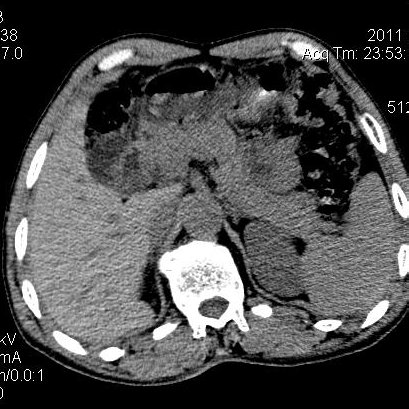

肝左叶发育异常

男性,55岁,骑摩托车摔倒后入院,自述右上腹疼痛

[backcolor=#FF0000]第一次诊断的时候也是这么肯定,可是床旁超声检查并没有发现明显异常,而且患者的一般症状都良好。还好临床只是保守治疗,没有立即手术,第二次复查的时候没有一点变化,又做了MRI检查,没有血肿,

这是一例肝左叶发育异常的,很个性吧~[/backcolor]